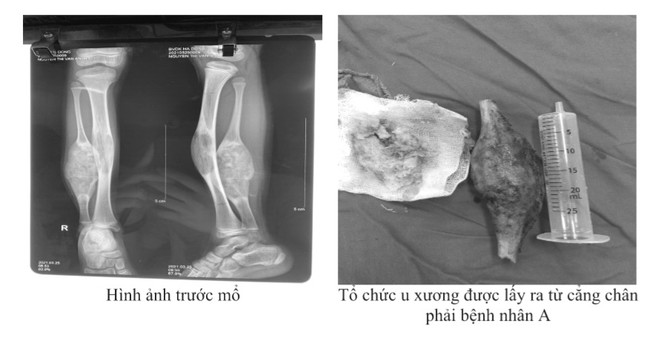

Bé N.T.V.A 10 tuổi (Chương Mỹ, Hà Nội) xuất hiện đau cẳng chân phải, gia đình nghĩ do con vận động chạy nhảy nhiều. Sau một thời gian tình trạng không đỡ, qua quan sát chân của bé, gia đình phát hiện 2 chân không to bằng nhau đã đưa đến khám tại Bệnh viện Đa khoa Hà Đông.

Qua khám và làm các xét nghiệm, bé được chẩn đoán loạn sản xơ xương cẳng chân phải.

Trong quá trình phẫu thuật, các bác sĩ đã tiến hành cắt khối u xương mác để lại màng xương, đục bỏ khối u xương chày, ghép đoạn xương mác đối bên khoảng 12 cm, cố định bằng các phương tiện hết hợp xương.

Sau phẫu thuật, bước đầu bệnh nhân ổn định, trục cẳng chân thẳng và chờ đợi thời gian liền xương để có thể tập đi. Bệnh nhân được tái khám định kỳ 1 tháng, 3 tháng, 6 tháng. Sau 15 tháng sau phẫu thuật xương liền tốt, bệnh nhân trở lại học tập và sinh hoạt bình thường.

Tưởng đau chân, bé 10 tuổi phát hiện với khối u xương chày lớn ảnh 2Tổ chức u xương được các bác sĩ lấy ra từ cẳng chân của bệnh nhân. (Ảnh: PV/Vietnam+)